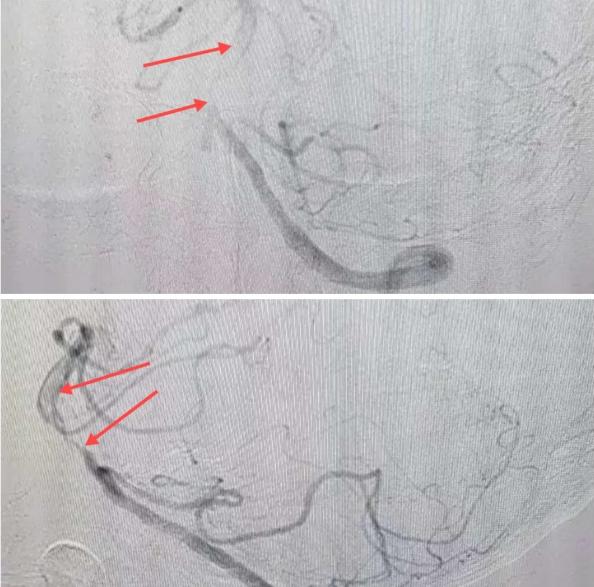

在經(jīng)造影后,主刀醫(yī)生腦一科副主任楊慶堂發(fā)現(xiàn)患者基底動脈下段重度狹窄且狹窄段以遠有大負荷血栓,其狹窄處考慮為動脈夾層,手術(shù)難度及風險較大。楊慶堂副主任在彭壯副主任醫(yī)師的協(xié)助下運用spaceman(太空人)技術(shù),中間導管抵近血栓抽吸配合支架拉栓,成功開通血管。再次造影可見基底動脈管腔明顯增寬,遠端血管顯影良好,且等待20分鐘后造影仍顯示血流通暢。楊慶堂副主任考慮到本次手術(shù)時間不宜過長,現(xiàn)患者基底動脈及分支前向血流維持良好,給予其抗栓藥物應用后結(jié)束手術(shù),并建議患者3個月后復查造影,明確其基底動脈夾層情況。

造影可見血管夾層和大量血栓形成